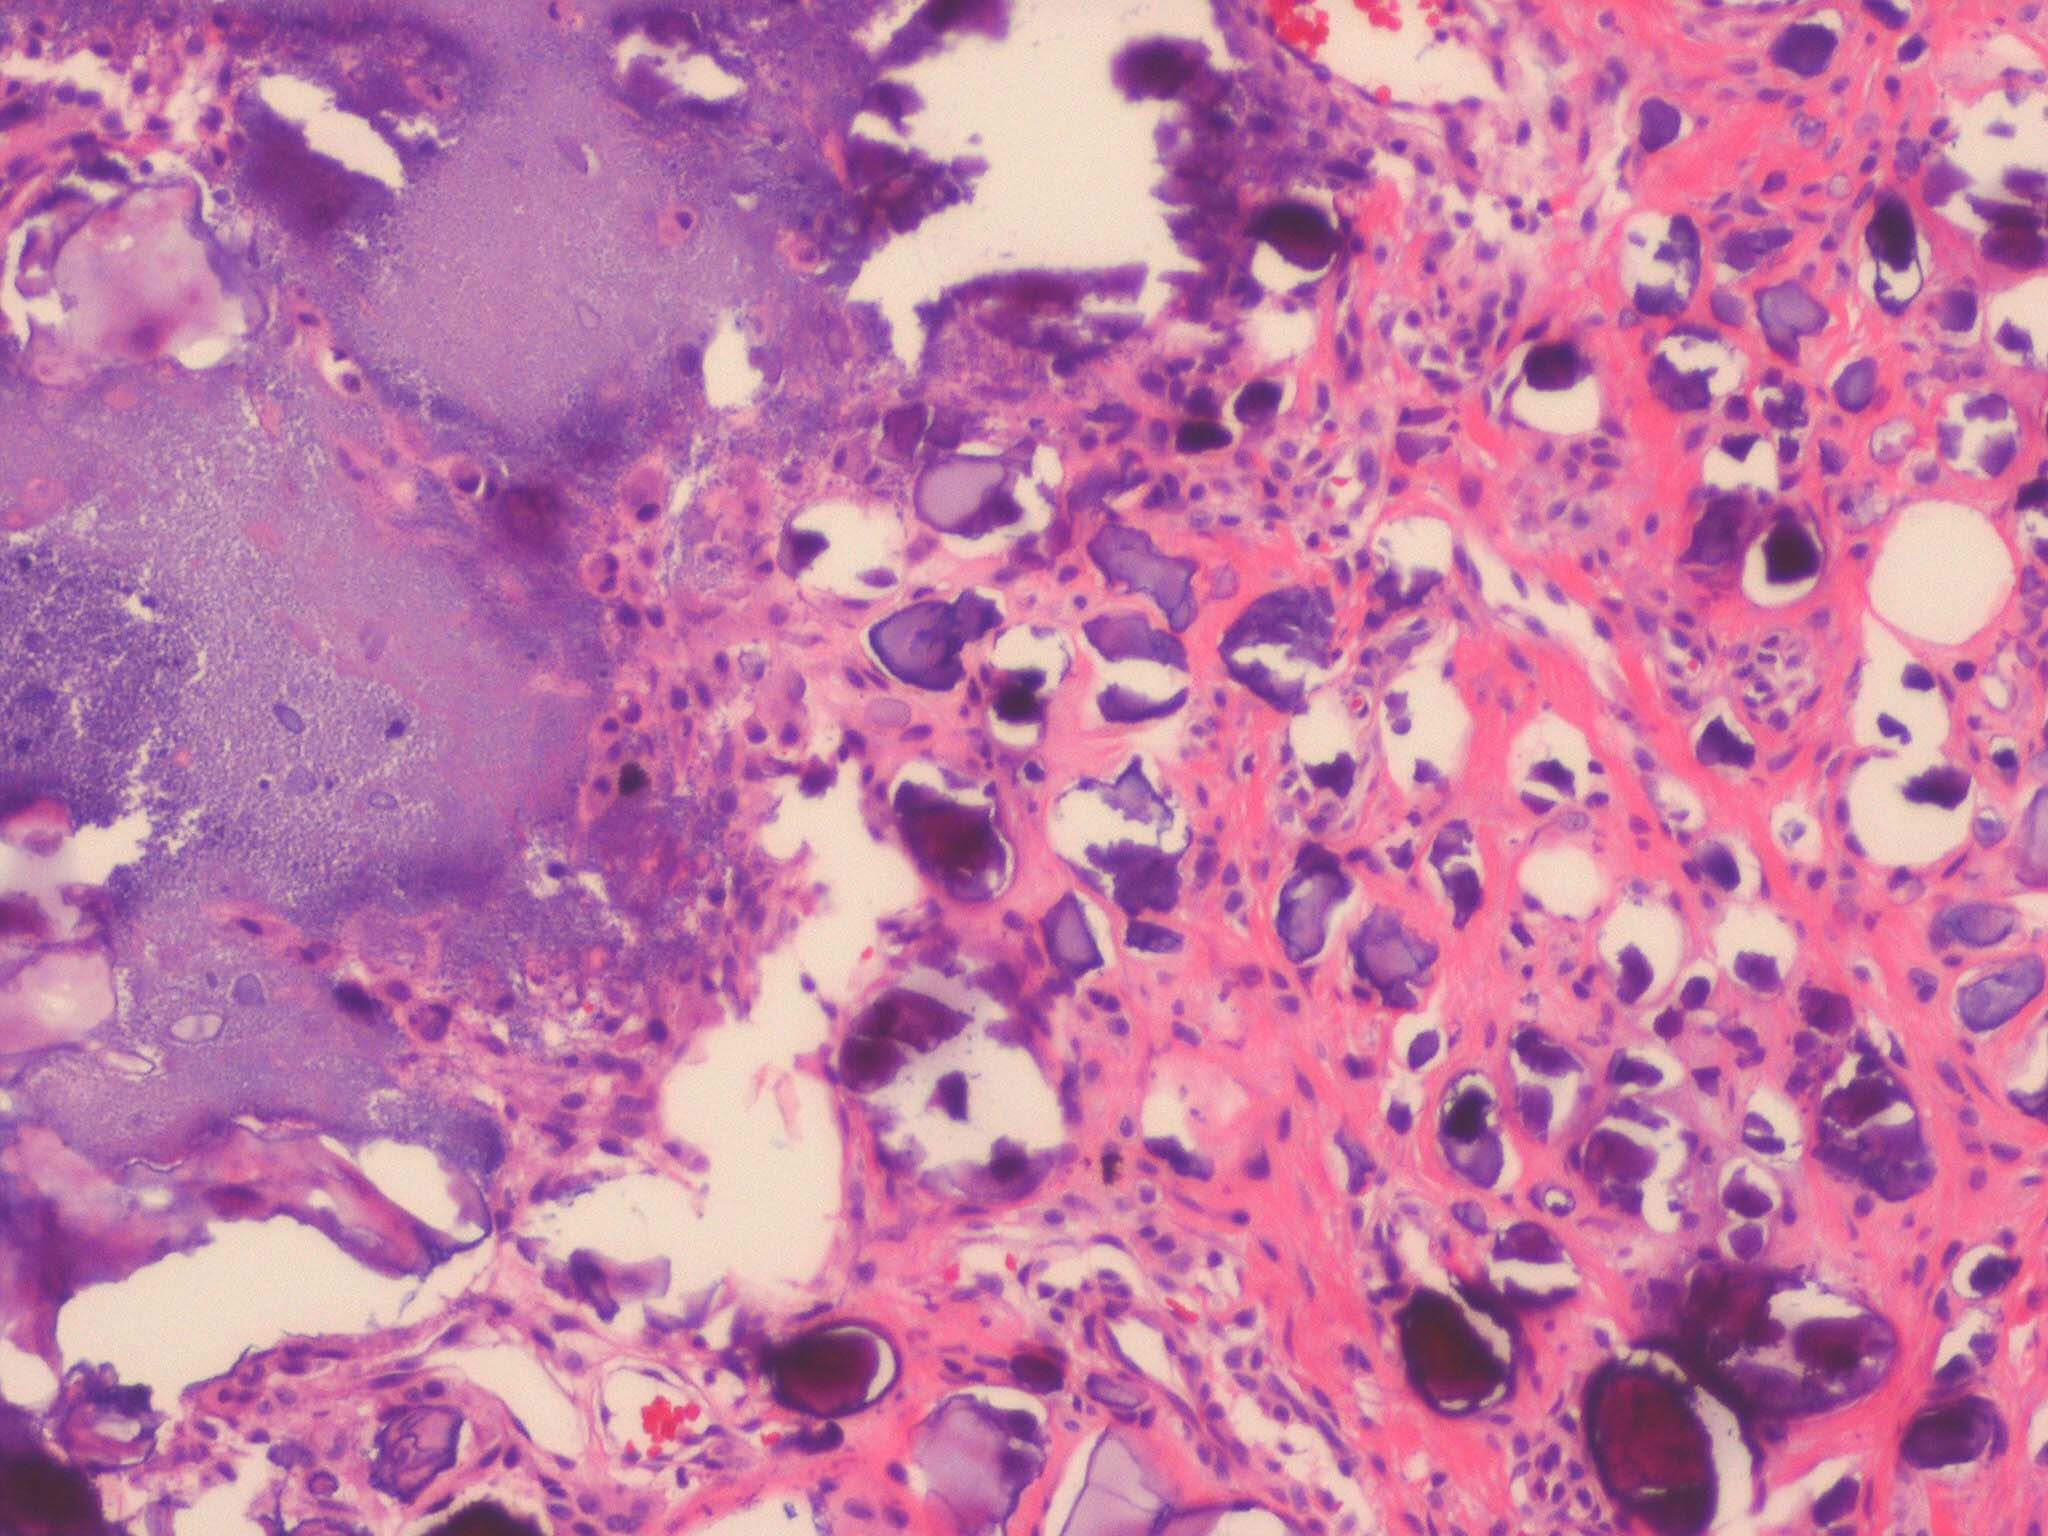

. Calcium deposits are recognized easily in histologic sections, because they stain deep blue with H&E. They stain black with the von Kossa stain for calcium phosphate. As a rule, the calcium occurs as massive deposits when located in the subcutaneous fat and usually as granules and small deposits when located in the dermis (Fig. 17-12). Large deposits of calcium often evoke a foreign body reaction; thus, giant cells, an inflammatory infiltrate, and fibrosis may be present around them .

The histologic changes in calciphylaxis include calcium deposits in the subcutis, chiefly within the walls of small­and medium-sized vessels . These deposits can be associated with endovascular fibrosis, thrombosis, or global calcific obliteration . The fully evolved disease process shows, in addition, areas of necrosis with a clean background or accompanied by neutrophils .

As in metastatic calcinosis cutis, the calcium in dystrophic calcinosis cutis usually is present as granules or small deposits in the dermis and as massive deposits in the subcutaneous tissue . A foreign­body giant cell reaction is often found around large deposits of calcium . The calcium deposits usually are located in areas in which the collagen or fatty tissue appears degenerated as a result of the disease preceding the calcinosis.